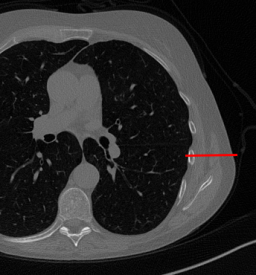

Here we present the results of RISING applied to the Mayo data set introduced in paragraph 4.1. As previously mentioned, we consider two sparse-view CT geometries, namely and . In Figure 4 we report the results for the protocol, achieved on one image of our test set. The top-left image represents the reconstruction. Even if only a small number of iterations are performed, the main structures of the abdomen are visible; however, the image is still blurry. In the image, shown in the upper-right corner, we notice that the TV regularizer has acted to totally eliminate the artifacts and noise, improving the uniformity of the image in the inner structures. When compared to the ground-truth solution in Figure 2, the contours of the details in appear slightly jagged, differently from where they are neat but, usually, corrupted by artifacts. The bottom row of Figure 4 shows the two and images, respectively from left to right. It is evident that has retrieved many details but it presents noisy components, reflecting the features of its target image . Our solution is less corrupted, since the low-contrast regions are correctly preserved and the noise is not visible. These observations are confirmed by Figure 5, which plots the intensity profiles taken over the red line in the second crop (Figure 2). In our approach (on the right) the CNN has accurately learnt the map of (8) and the red profile mostly overlaps the black one. On the contrary, the profile (on the left) is more distant from its target reference.

In Figure 7 we plot for these experiments, the same profiles of Figure 5.

In the left graph, we analyse the performance of LPP approach: the reconstruction gets values quite close to the GT, but it does not fit well the target black line.

In the right graph, we analyse the performance of RISING approach: the solution almost overlaps the target profile, confirming that the network has correctly learned.